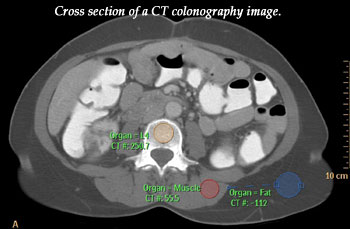

The research looked at the technique of CT colonography which takes images with X-rays to provide cross-sectional snapshots of various parts of the body.

They wanted to see if in scanning the abdomens of these 35 people, CT colonography would also collect data on the condition of their spine. They hypothesized that this spine data would allow them to measure bone mineral density - an indicator of risk for osteoporosis or "porous bone," a disease in which bones become fragile and prone to fracture. According to the National Institutes of Health, some 10 million Americans already have osteoporosis and 34 million more have low bone mass and are at increased risk for the disease.

Aslam and his colleagues discovered that CT colonography can indeed evaluate people for osteoporosis. The study showed excellent agreement between the CT estimates of bone density and estimates derived from dual-energy X-ray absorptiometry (DEXA), the current clinical standard bone density screening tool.